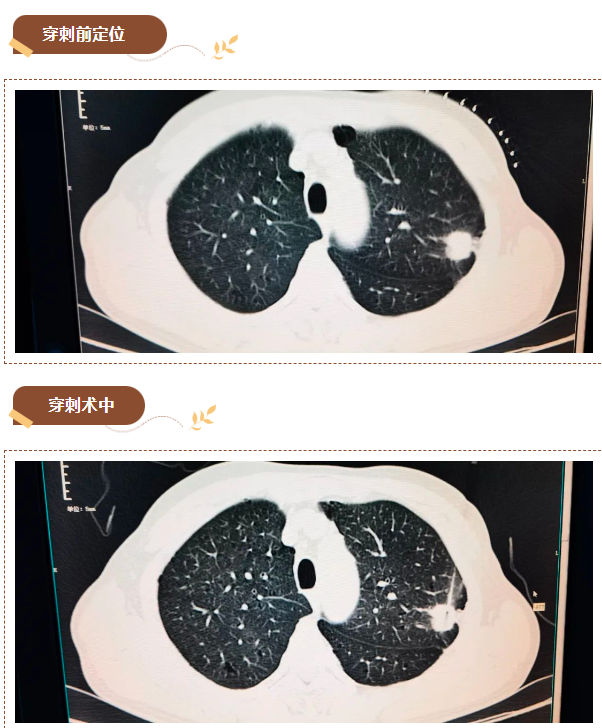

患者胡先生(化名)于院外体检发现左肺上叶占位性病变,于近日在家人的陪同下到我院就诊。入院后,接诊医师对其进行了肺部CT检查,提示肺部结节,有可能为“肿瘤性病变”可能。胡先生心理十分焦虑,希望能尽快明确诊断。

经会诊,决定以最小的微创检查方式明确诊断肿瘤性质,为患者实施“CT引导下行经皮肺穿刺活检术”。

遂完善胡先生的术前检查,并对可能出现的并发症做了充分评估后,放射科医生在螺旋CT机精确引导下进行CT引导下穿刺活检,成功取得病检标本,整个手术过程顺利,用时仅20分钟,术中和术后患者无明显不适,病理结果提示(左肺上叶穿刺组织)腺癌。